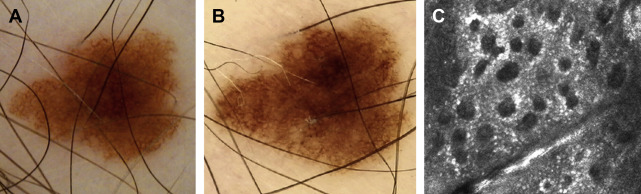

SDDI involves capturing dermoscopic images of lesions over time in order to identify changes concerning for melanoma and can be used in 2 complementary ways. The first method involves repeating dermoscopic images of skin lesions at regular intervals for detailed comparative analysis, which when combined with TBP has been referred to as “digital follow-up” and has been shown to enable recognition of melanomas that lack diagnostic clinical or dermoscopic features at baseline evaluation ( Fig. 2 ). SDDI can also be used as a second-level screening evaluation of specific lesions with borderline features. When used in this manner, SDDI dramatically reduces the number of biopsies of benign lesions compared with use of dermoscopy alone ( Fig. 3 ). Access to SDDI compared with dermoscopy alone has also been associated with a 35% reduction in the cost per melanoma excised in a 1-year retrospective observational study in Belgium.

New or changing skin lesions with equivocal features after dermoscopic or SDDI examination can undergo analysis with RCM, which noninvasively allows for cellular assessment of the epidermis and superficial dermis at a resolution approaching histologic detail (see Fig. 2 ; Fig. 4 ). The reported sensitivity and specificity of RCM for melanoma among experts are estimated to range from 91% to 96.5% and 68% to 94.1%, respectively. Used as a second-level screening test, RCM has been shown to improve diagnostic accuracy for melanoma and to prevent unnecessary biopsies of benign lesions. RCM may be particularly useful for evaluation of amelanotic, facial, or dermoscopically nonspecific lesions. Studies have specifically demonstrated the impact of RCM as a screening evaluation after SDDI. In this setting, it can prevent nearly 70% of unnecessary biopsies of benign nevi found to have changes that warrant removal.

Nevi and melanomas can display similar morphologic changes during dermoscopic monitoring and may even grow at similar rates. Indeed, studies have demonstrated that nevi and melanomas removed during SDDI are often clinically and dermoscopically indistinguishable and that change alone permitted melanoma identification. However, the most relevant changes associated with melanoma during SDDI are asymmetric enlargement, appearance of focal or eccentric new structures (ie, “dermoscopic island”), or the appearance of atypical focal dermoscopic features such as vessels or regression features. Changing lesions with features concerning for melanoma should undergo biopsy, whereas lesions with equivocal features can undergo RCM or repeated dermoscopic imaging over a longer or sometimes indefinite time interval ( Fig. 5 ).